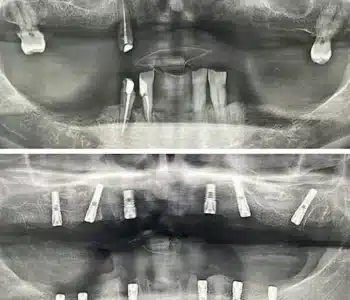

Dr. Seden Aksu is a specialist in modern implantology and surgical dentistry with extensive experience in the management of complex clinical cases. In her practice, she applies comprehensive surgical planning, minimally invasive techniques, and advanced regenerative technologies aimed at restoring both the function of the dentoalveolar system and the aesthetics of the smile. Dr. Aksu has significant experience in performing implant procedures, bone augmentation, and periodontal surgery, including the treatment of patients with severe bone loss. The primary goal of her work is to achieve stable, long-term outcomes in implant rehabilitation and the restoration of oral tissue health.